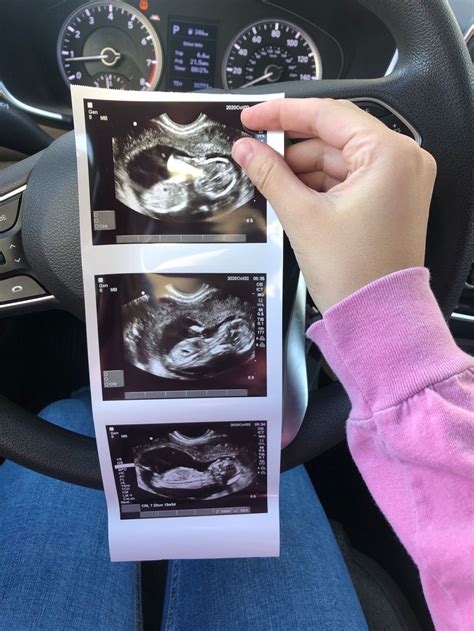

After the 13-week gestation ultrasound, the healthcare provider will review the images and measurements to assess the baby's development and health. The results will be discussed with you, and any necessary follow-up steps will be outlined. Here are some key points to consider:

• Normal Findings: If the ultrasound reveals normal findings, it is a reassuring sign that the baby is developing as expected. However, it is essential to continue with regular prenatal care and follow-up appointments.

• Follow-Up Appointments: Based on the ultrasound results, your healthcare provider may schedule additional appointments or tests to monitor the baby's development and address any concerns.